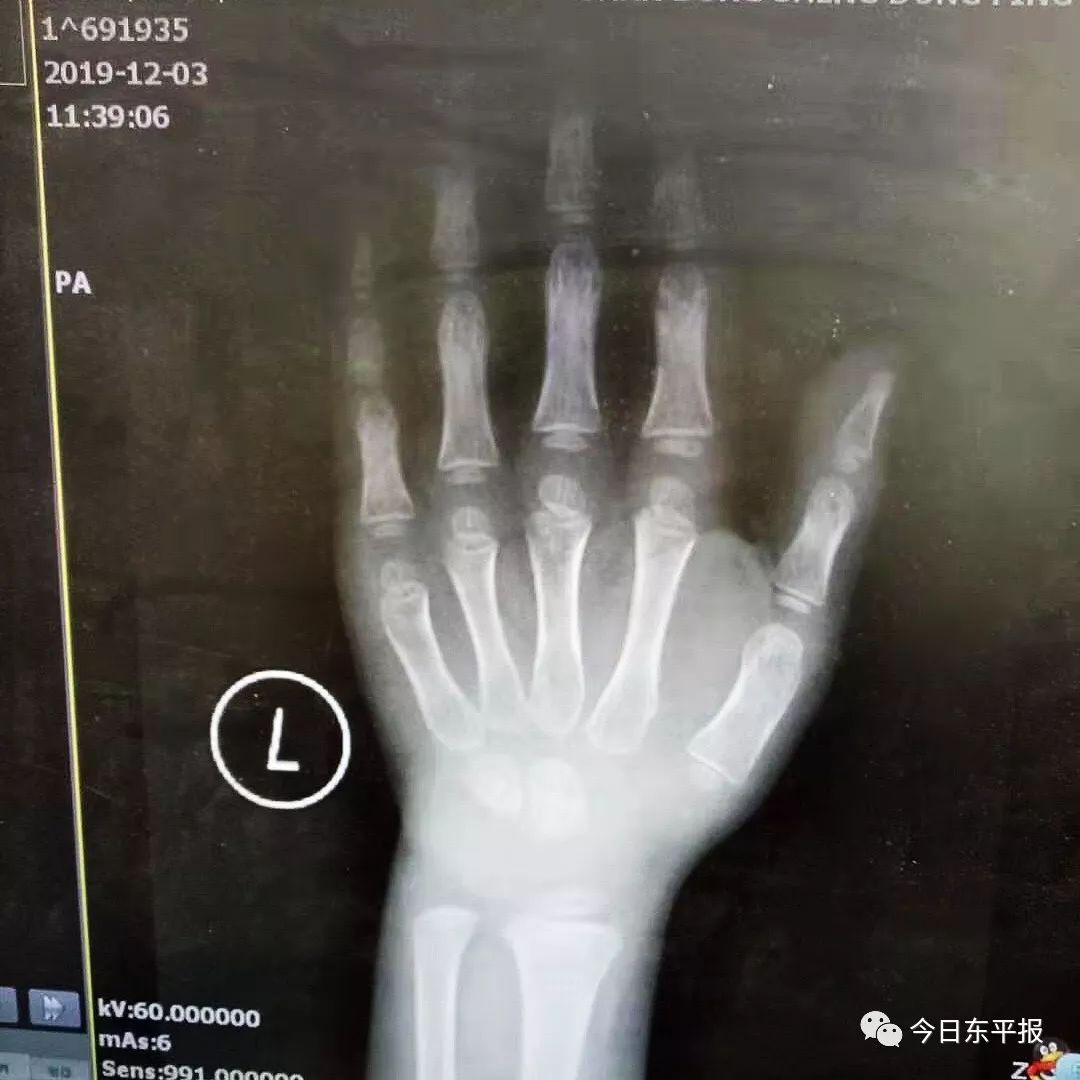

該患兒實際年齡5歲,身高97.5cm,相當于3歲兒童身高,宋主任在查房時詳細向家長介紹了影響孩子身高的因素,并建議行骨齡片及垂體核磁共振檢查,以進一步評估孩子的發(fā)育狀況。骨齡片顯示骨齡2歲,核磁共振結果提示垂體體積略小。孩子骨齡明顯落后,宋主任建議進行生長激素激發(fā)試驗:首先空腹抽血,查生長激素,同時測肝功、腎功、甲狀腺功能,然后讓孩子口服左旋多巴后30min、60min分別抽血監(jiān)測生長激素。此例生長激素激發(fā)試驗成功的開展,標志著東平縣人民醫(yī)院兒科內分泌專業(yè)進入到了一個新的起點,為兒童生長發(fā)育門診的規(guī)范化發(fā)展必將起到積極的推動作用。下一步,在兒童性早熟、兒童肥胖的診治上將借助山大二院人才、技術平臺,發(fā)展成該院的優(yōu)勢專業(yè)。